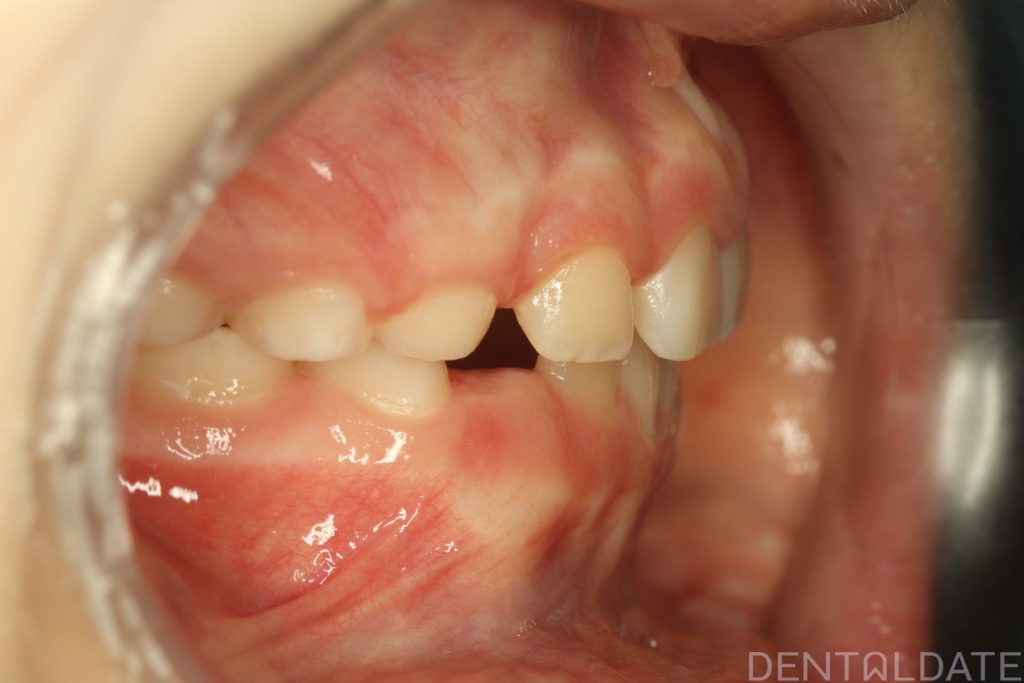

Parents sought an orthodontic consultation due to concerns about the aesthetics of their child’s smile.

To achieve harmony between function and aesthetics, a Haas appliance was used, followed by a myofunctional appliance.